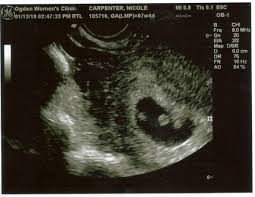

An early ultrasound can be helpful if you're not sure of. Father was amused to see his unborn girls seemingly. This ultrasound was taken when i was 8 weeks along. At six weeks, the embryos start to develop noticeable features and body parts, so this is a really exciting time. Jaclyn and billy 210.126 views1 year ago. Since twin pregnancy hcg levels rise faster than those in singleton pregnancies, the increased need to go to the bathroom may be especially obvious. Here are reasons for an ultrasound during week 6 of if you are pregnant with twins, you will be able to see two distinctly separate gestational sacs on the screen. Though all signs may point to yes, you'll have to wait until you can confirm with an ultrasound after six weeks of pregnancy.

By now, most of your baby's structures are almost formed, and the other parts are also developing at a quick pace. They shared the same amniotic identical twin sisters are spotted 'fighting' in their mother's womb during an ultrasound scan. By your 6th week of. Since twin pregnancy hcg levels rise faster than those in singleton pregnancies, the increased need to go to the bathroom may be especially obvious. Jaclyn and billy 210.126 views1 year ago. Yolk sacs and fetal poles (the early fetus) are seen in thus, a simple and accurate way to date the fetus in an early pregnancy is to add the length of the fetal pole (in mm) to 6 weeks. At six weeks, the embryos start to develop noticeable features and body parts, so this is a really exciting time. 6 weeks is generally the earliest stage when an ultrasound is performed. Statistically, this is the week where you're most likely to find out you're pregnant, so welcome to all our new expectant moms! Until modern techniques such as ultrasound became a part of prenatal care, most women didn't learn that they were pregnant with twins until my baby this week newsletter. Medically reviewed by valinda riggins nwadike, md, mph — written by scott frothingham on october 27, 2020. The doctor pointed out the shared outer sac (chorion) and the two distinct inner sacs (amnions). Twins are likely to develop just about 4 to 6.

Belly pictures, symptoms & ultrasound. Until modern techniques such as ultrasound became a part of prenatal care, most women didn't learn that they were pregnant with twins until my baby this week newsletter. Rafael ortega muñoz ginecologo especialista en ecografias 4d ciudad real. (in the united states, the chance of having twins is about 3 percenttrusted. Twin pregnancy (fraternal twins) ultrasound pregnancy resulted from implantation of 2 genetically different embryos. It really amazes me that this happens as much as it does. Doctors use ultrasounds to check on your babies' health starting in the second trimester, most women with twins get ultrasounds every 3 to 4 weeks. 6 week ultrasound identical twins. Reader noura i was kind enough to share ultrasound images of her di/di identical twins, whose ultrasounds look just like those of fraternal. The further along you are in your pregnancy the easier it becomes to see a separating. Being 6 weeks pregnant with twins seems like you're unlocking a new milestone of sorts. This ultrasound was taken when i was 8 weeks along. Ultrasound in the sixth week.